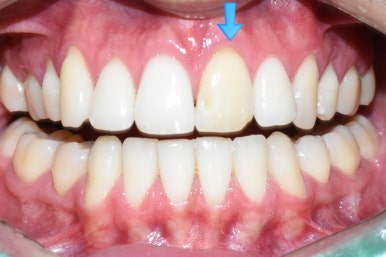

치료전후 사진

위 앞니 변색 치아 하나 치료 전(왼)-치료 후(오른쪽 사진)

다행히 처음 끼워드린 크라운에 환자분이 색상이나 모양 매우 만족하셔서

크라운을 다시 수정보내는 일 없이 한번에 장착하였습니다.